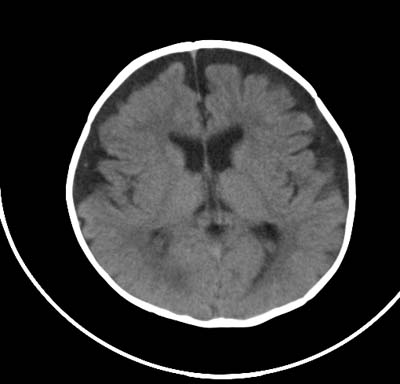

以下是引用影象小泰斗在2008-6-30 15:57:00的发言:[br]双侧额、颞部蛛网膜下腔增宽,纵裂加深, 支持外部性脑积水![br] 双侧基底节点状钙化!

以下是引用jiangjing在2008-6-30 17:19:00的发言:[br]双侧额、颞部蛛网膜下腔增宽,纵裂加深, 支持外部性脑积水![br] 双侧基底节点状钙化![宫内感染形成可能]